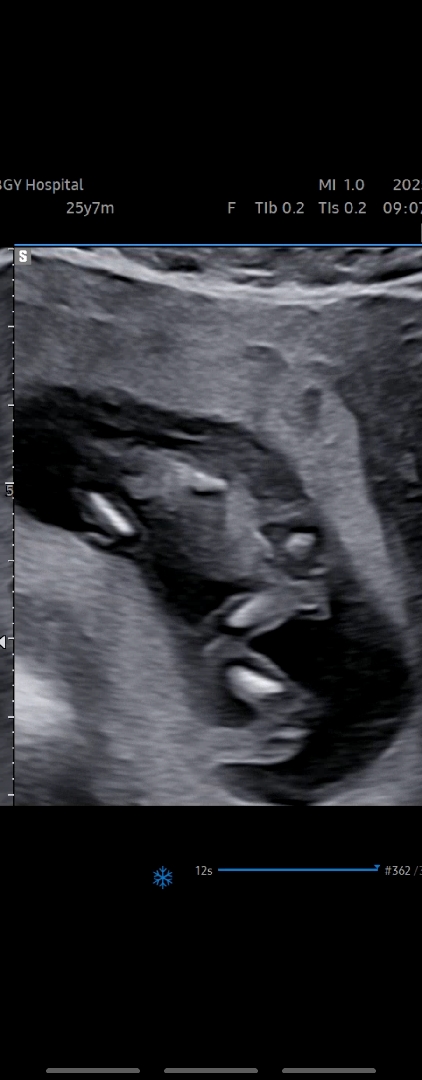

아기가 등지고 양반다리하고 잇다가 겨우 비스듬하게 하도 찍엇는데 남자아이라고하기에는 모양이 로켓이 아닌 삼각이라 꼬리뼈인지해서 올려봐요! 다들 보시기에는 어떻게 보이시나요????

12주는 각도법으로 봐야 알아요. 남아도 여아도 생식기가 밖으로 나와있어서요!